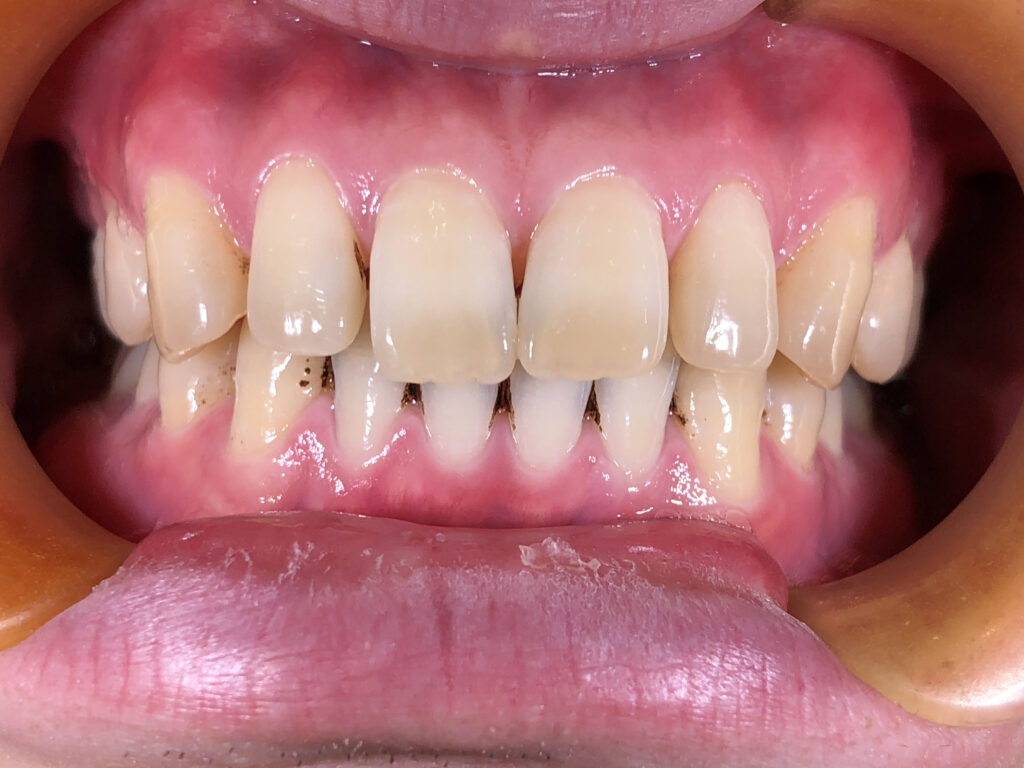

正面

治療前

患者様は上下の横の前歯の隙間を気にされており、「できれば完全に隙間を閉じたいが、ある程度改善されればよい」とのご希望で来院された。 インビザライン矯正では、前歯の近接移動を中心に計画し、効率的に隙間を閉鎖するため犬歯・小臼歯にアタッチメントを付与。また、閉鎖後の歯肉退縮やブラックトライアングルを最小限に抑えるため、歯根の平行性を意識して移動を行った。 治療により上下前歯の隙間は良好に閉鎖し、咬合も安定。審美的な改善とともに、発音や清掃性の向上にもつながった。 |